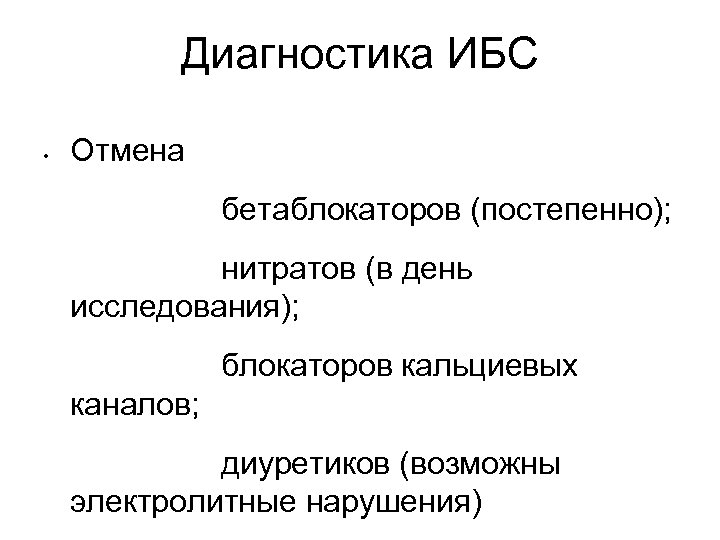

Диагностика ИБС • Отмена бетаблокаторов (постепенно); нитратов (в день исследования); блокаторов кальциевых каналов; диуретиков (возможны электролитные нарушения)

Диагностика ИБС • Отмена бетаблокаторов (постепенно); нитратов (в день исследования); блокаторов кальциевых каналов; диуретиков (возможны электролитные нарушения)